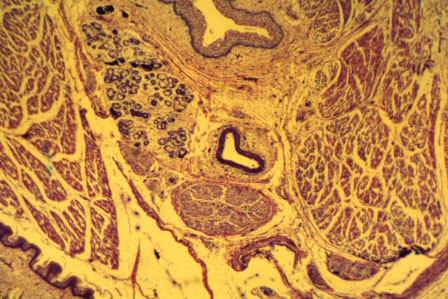

K-slide 11: This is a higher magnification of slide 10, showing the sublingual gland, Wharton's duct and the lingual nerve.